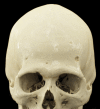

This is a case of a 22-year-old, HIV-negative, male patient with asymptomatic syphilitic osteomyelitis of the skull in the context of secondary syphilis. The diagnosis was made based on serology as well as CT and MRI scans. CT volumetric data was post-processed with cinematic rendering, which is a novel algorithm that allows for a photorealistic visualization of the lesions. Imaging and follow-up scans after treatment confirmed the diagnosis without the need to perform invasive procedures such as a biopsy.